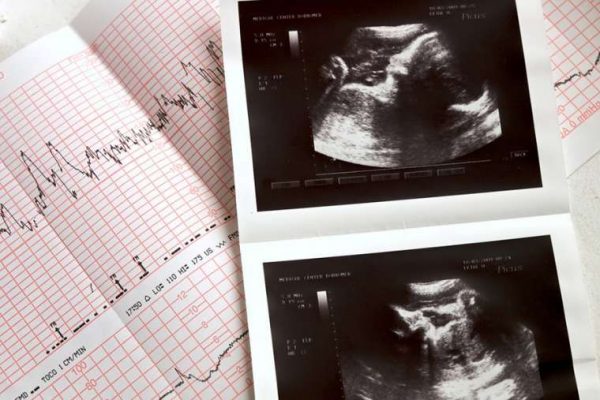

Study: Texas fertility rate rose after ‘Heartbeat Act’ — By: Catholic News Agency

null / Credit: liseykina/Shutterstock CNA Staff, Jan 30, 2024 / 11:30 am (CNA). The fertility rate in Texas rose by a statistically significant amount in the wake of the state’s pro-life laws, a University of Houston study has found. Texas, which prohibits abortion except in the case of medical emergencies, was among the numerous states with “trigger…